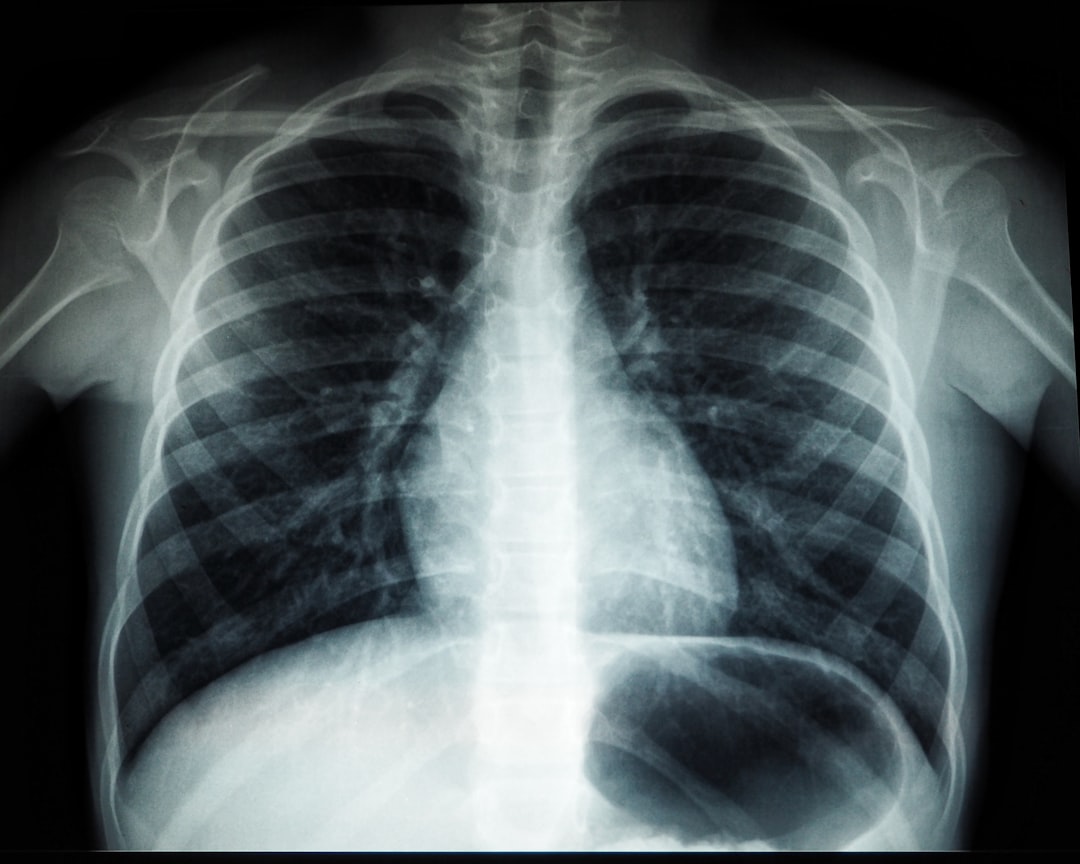

검사 결과가 나오는 과정은 기대감과 불안이 교차하는 순간입니다. 잠복결핵 검사 결과지를 통해 결핵균에 감염된 여부를 알게 됩니다. 결과가 양성으로 나올 경우 마음이 무거울 수 있으나, 현실적으로 치료가 가능한 단계라는 것을 잊지 말아야 합니다. 적극적으로 대응하면 문제를 해결할 수 있습니다. 잠복결핵 검사 확인서는 이렇게 중요합니다.

양성 판정은 고통스러운 진실일 수 있지만, 당신의 건강 지키기에 중요한 첫걸음입니다. 언제든지 전문가와 상담하며, 적절한 치료를 통해 일상생활로 돌아갈 수 있도록 노력하는 것이 중요합니다. 기억하세요, 결핵에 대한 이해가 있다는 것은 이미 치료의 반을 아는 것과 같습니다.

검사 결과 확인 후, 해당 확인서의 유효기간을 체크해야 합니다. 일반적으로 결과는 1년 이상의 유효기간을 가집니다. 그러나 특정 상황이나 추가 진료가 필요할 경우 재검사가 될 수 있으니 항상 약속된 일정을 지키도록 하세요! 잠복결핵 검사 확인서 재발급이 필요한 경우에도 해당 기관에 문의하여 제출할 수 있습니다.